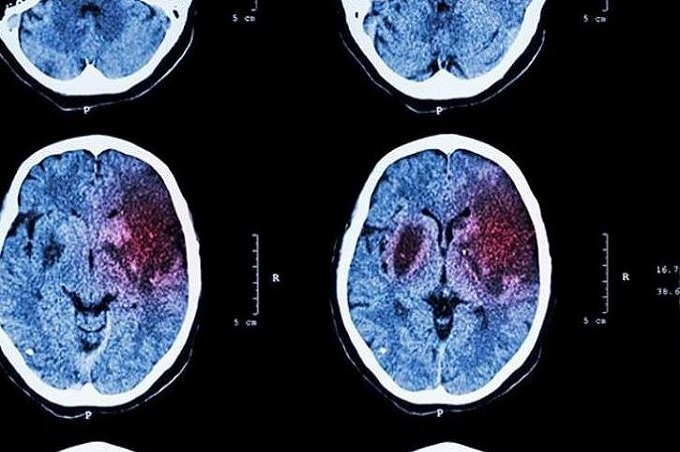

Accident cerebrovascular PPAL